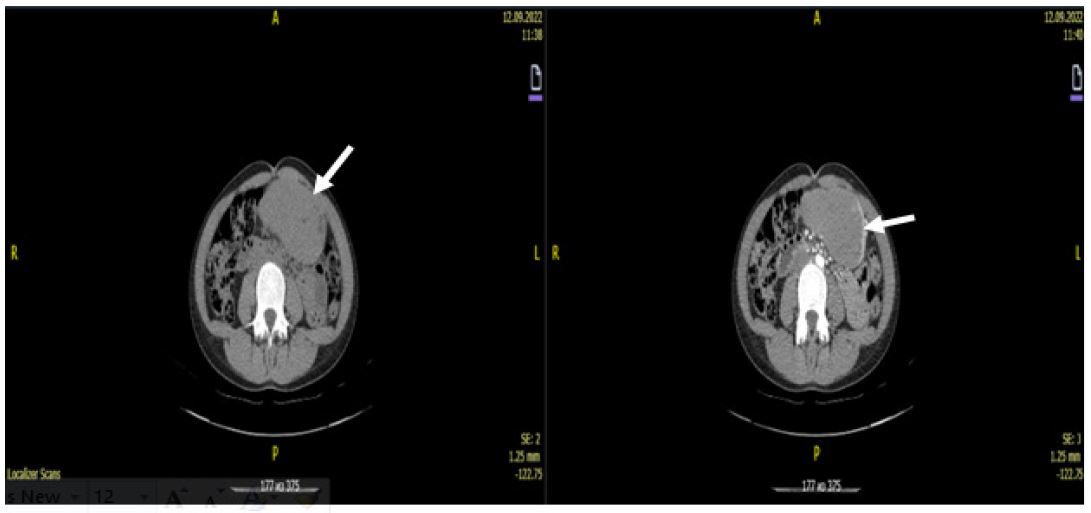

Computed tomography of the abdominal cavity revealed a tumour of the angle and outlet of the stomach (most likely lymphoma), with infiltration of the perigastric tissue (Figures 1,2).

Figure 1: Tumors of the angle and antrum of the stomach with clear contours.

Figure 2: Tumor of homogeneous structure, without signs of invasion into neighboring organs and lymphadenopathy. Diffuse circular thickening of the walls of the antrum of the stomach is noted.